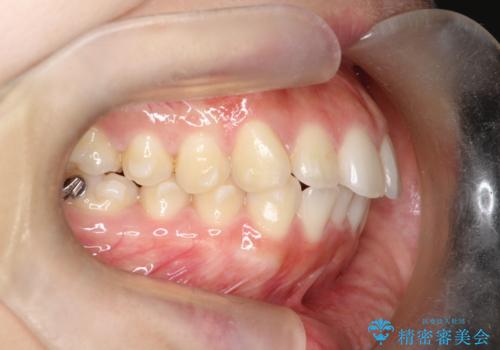

下顎前歯の叢生を短期間で改善

- 患者様は、下顎前歯のガタガタ(叢生)の改善を希望して来院されました。診断の結果、非抜歯で治療可能であると判断し、透明で目立たないインビザラインを使用する矯正治療計画を立案しました。短期間での治療を希望されていたため、IPR(歯間削合)を併用してスペースを確保しながら、効率的に歯を並べることを目指しました。

治療では、インビザラインを用いて計画的に歯を移動させ、短期間での歯列改善を実現しました。IPRを行うことで、抜歯をせずに必要なスペースを確保し、歯列全体を整えました。治療中は、装置の適切な装着時間を守ることが重要であり、患者様にも継続的な協力をお願いしました。また、歯肉や歯根への負担を最小限に抑えるため、歯の移動を慎重に管理しました。結果として、短期間で下顎前歯の叢生を改善し、自然な見た目と機能性を兼ね備えた歯列を実現できました。